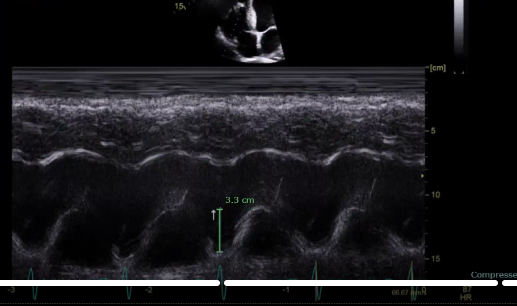

what is the TAPSE and S’ measurements

TAPSE and S’ is the longitudinal function measure how well the muscle is moving up and down

our TAPSE and S’ should match normal numbers b/c they are measuring the same thing so it should match normal

what is the measurement for

this is going to be the RV systolic function, this is the TAPSE measurement from the bottom of the hill to the top of the hill the normal values for TAPSE is >1.7- <2.4